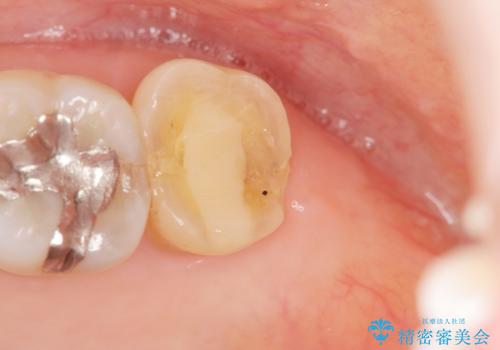

- 根管治療ののち、そのままになっていた歯のクラウン製作を希望され来院されました。

クラウンの将来的な虫歯の再発を防ぐために周囲の歯ぐきを切除することで歯の高さを出し安定した歯周環境にしたのち噛み心地の良いゴールドクラウンを製作します。

クラウンを装着した歯の虫歯の再発を防ぎ長い予後を期待するために削った箇所をしっかりとかぶせる適合の良さが必要はもちろんですが、セメントの漏洩を防ぐためにクラウンの十分な支台高径を歯周外科を行い獲得しました。